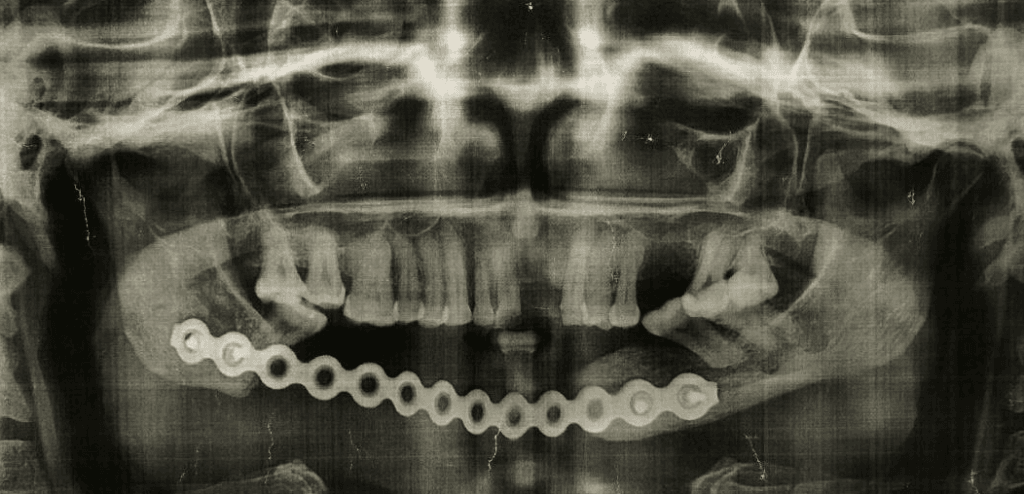

Pour cette première (à la fois en Guinée et à la fois par Enfants Du Noma), le cas a été bien choisi, sans comorbidité associée, et de façon à ne pas être confronté à des soucis de dénutrition ou d’anémie. Il s’agissait d’une patiente guinéenne de 42 ans, qui avait déjà bénéficié à Conakry il y a un an de l’exérèse d’un très volumineux améloblastome (tumeur bénigne) de la mandibule par le Pr Rahiou Diallo. La perte de substance osseuse avait été maintenue par une plaque métallique, mais sans apport osseux. Cette plaque avait fini par s’exposer dans la bouche de la patiente, et il fallait donc recourir à une reconstruction osseuse.

L’intervention a consisté en le prélèvement du péroné droit (fibula) de la patiente, avec de la peau de la jambe pour reconstruire la peau du menton, et surtout avec son artère et ses veines qui ont été « rebranchés » (micro-anastomoses) sous microscope à des vaisseaux au niveau du cou, pour que tous ces tissus soient revascularisés. Il a fallu 2 morceaux de péroné pour reconstruire la forme de la mâchoire, un pour le menton, et l’autre pour la branche horizontale droite.

Dans les suites de ce type de reconstruction, la surveillance doit être stricte, avec des objectifs stricts concernant notamment la tension artérielle et le taux d’hémoglobine, de façon à ce que les micro-vaisseaux rebranchés ne se « bouchent » pas par un thrombus, ce qui aurait nécessité une ré-intervention en urgence.

Rien de tout cela n’est heureusement survenu. Les suites ont été extrêmement simples et la patiente a été tellement rassurante sur l’ensemble des critères de surveillance, que nous avons autorisé sa sortie dès le 7ieme jour post-opératoire.